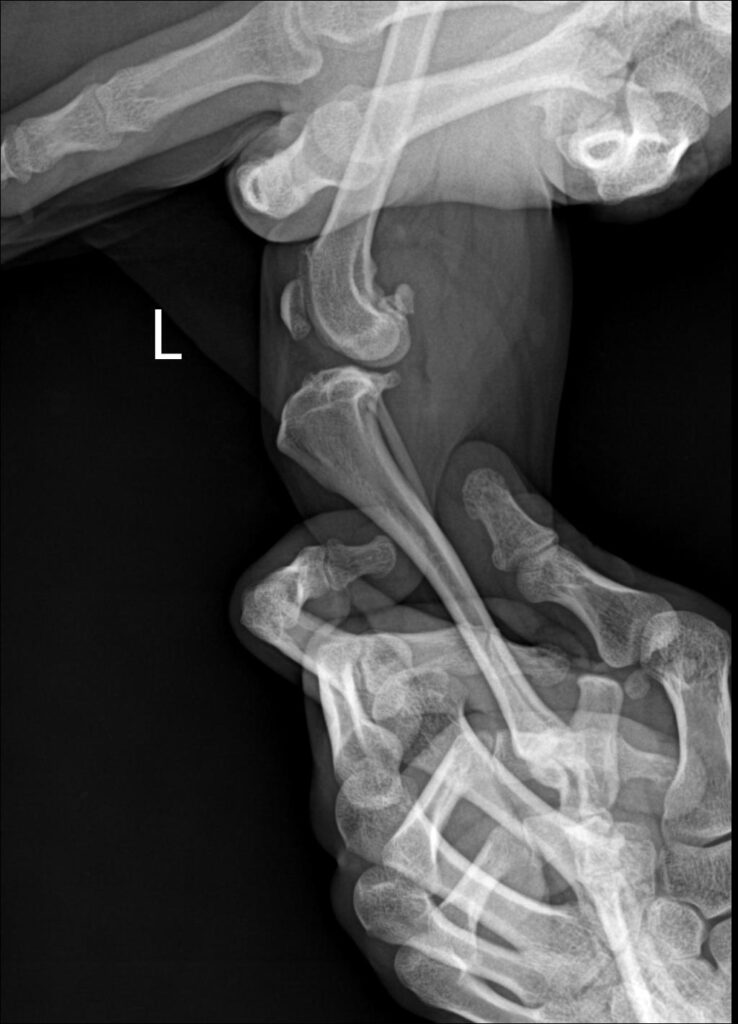

X-ray 검사

십자인대 파열된 우측/ 좌측 방사선 사진 / 출처: 미래동물의료센터

엑스레이 검사상 무릎 관절에서 drawer sign이 관찰되었으며, 십자인대 파열로 진단되었습니다. 처음 내원 당시에는 좌측 십자인대 파열로 진단되어 TPLO 수술을 진행하였고, 수술 후에는 비교적 안정적인 보행 상태를 유지하며 잘 지내던 환자였습니다.

그러나 좌측 TPLO 수술 후 수개월 경과 뒤, 반대쪽인 우측 후지에서 다시 파행이 발생하였고, 검사 결과 우측 십자인대 파열이 확인되어 우측 십자인대 TPLO 수술까지 진행하게 되었습니다.